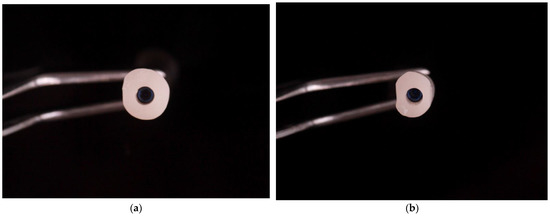

2. Materials and Methods